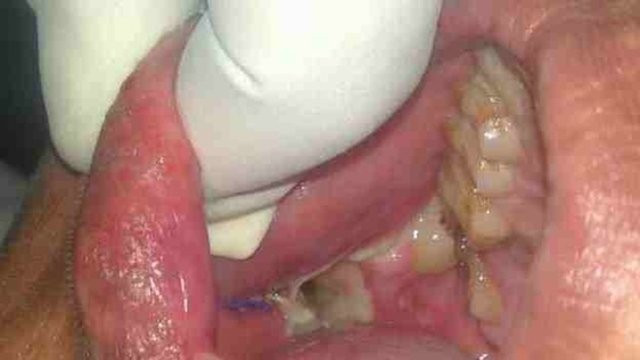

Hindistan'da yaşayan 17 yaşındaki Ashik Gavai, diş problemleri nedeniyle diş hekimine başvurdu.

Diş hekimlerini dehşete düşüren gencin ağzından tam olarak 232 tane diş çıkarıldı.

Ameliyatı yedi saat süren Gavai'nin durumunun iyi olduğu belirtildi.